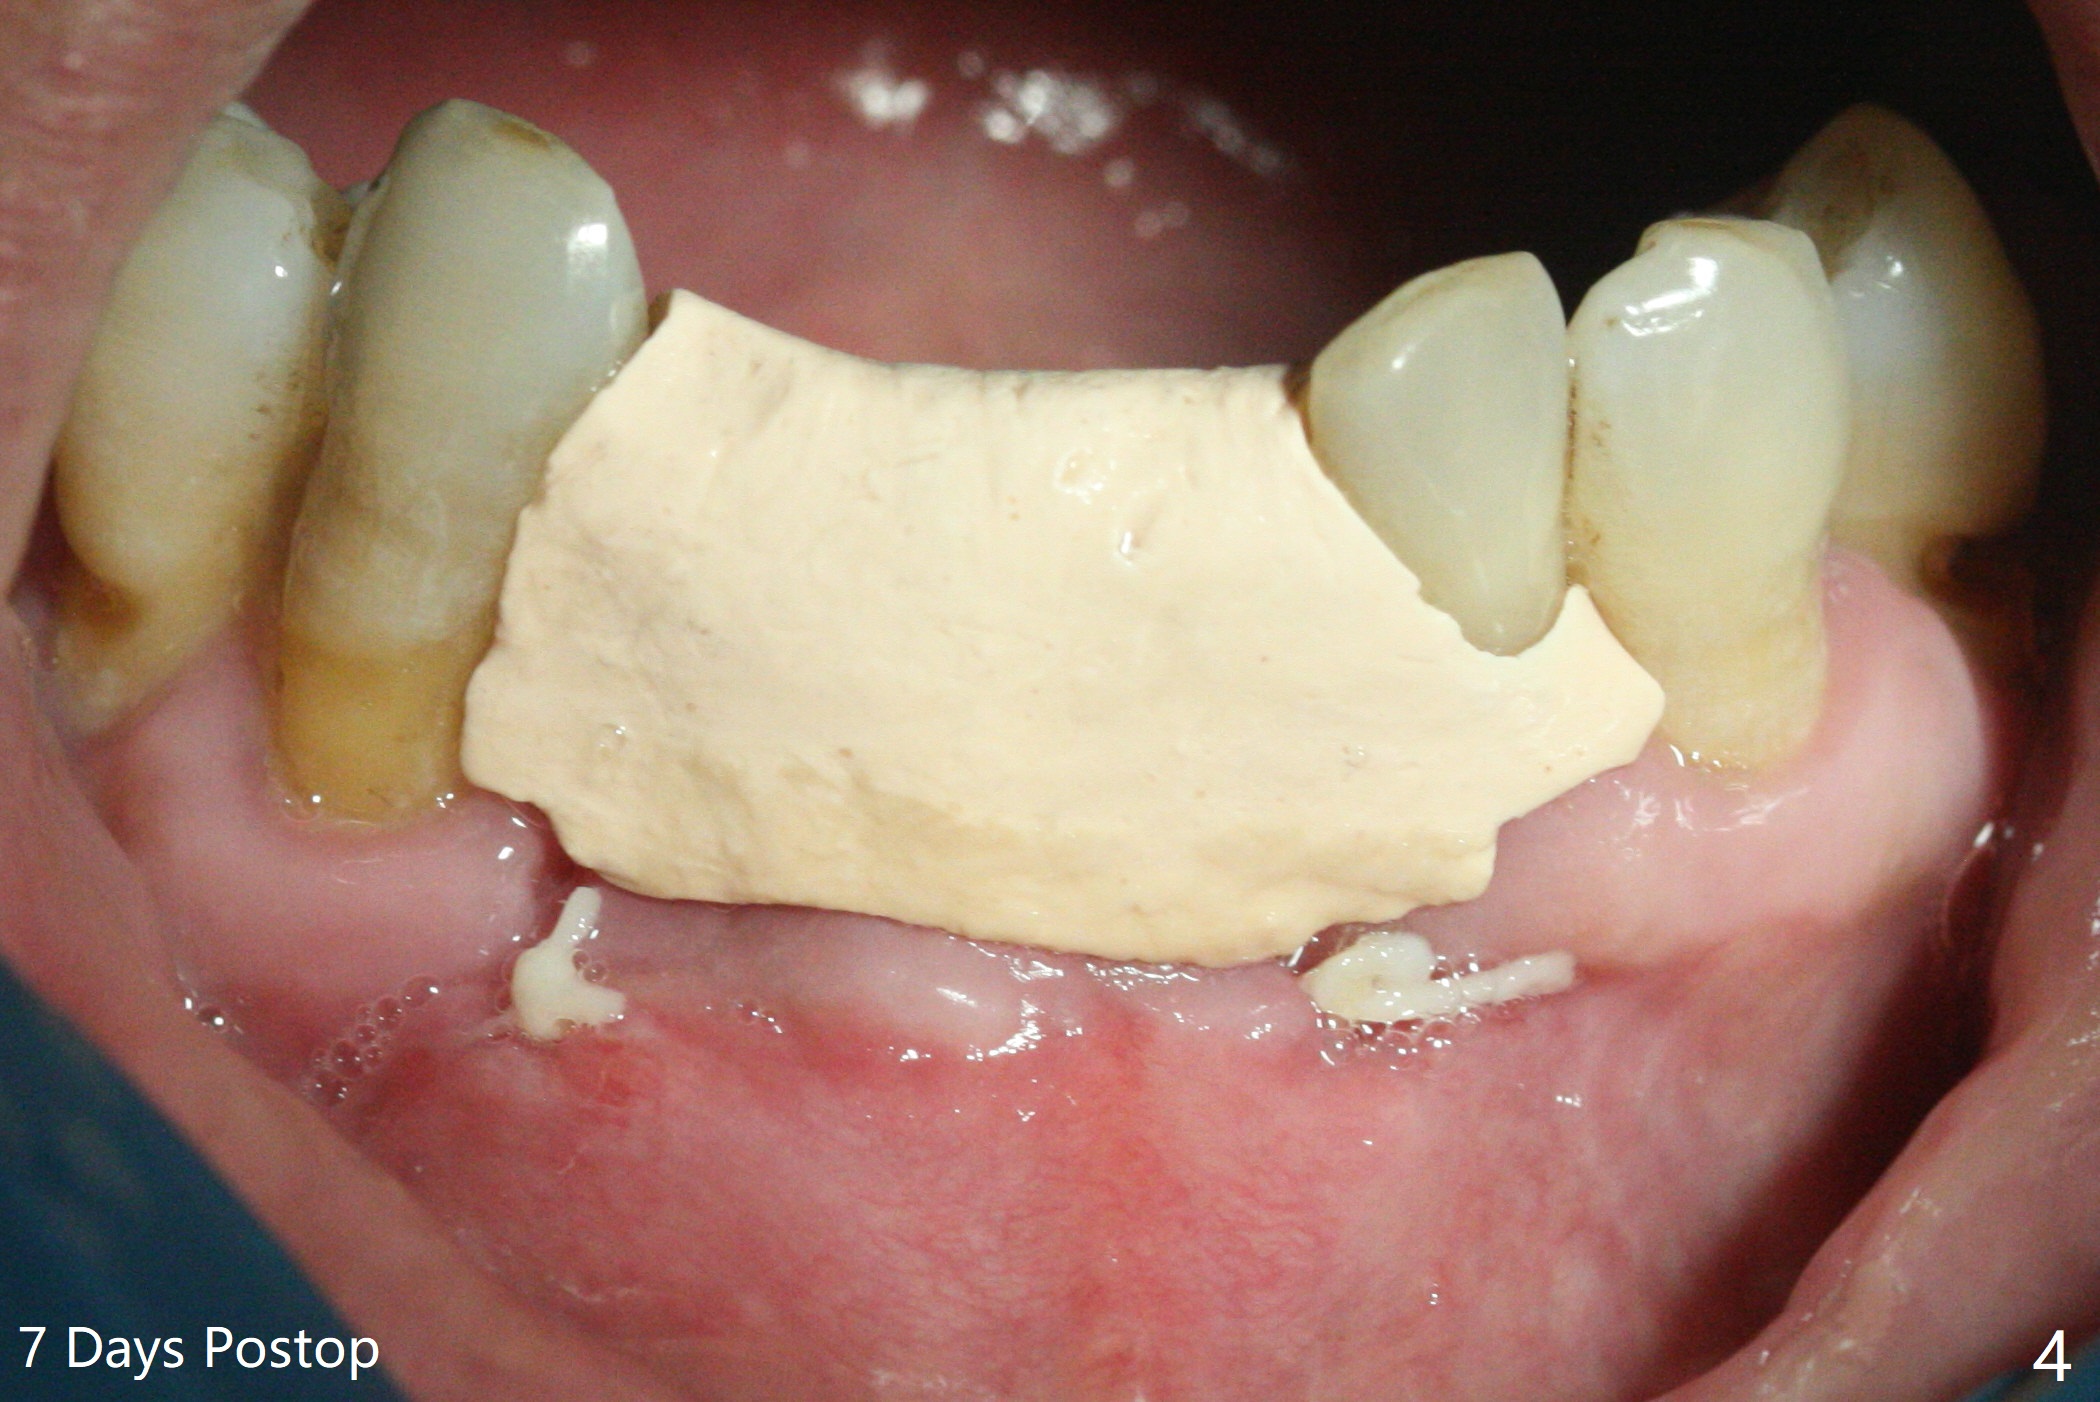

After placement of implant at #30 with high torque, osteotomy is prepared with 2.2 mm drill at #24 (M) first (Fig.1 before flap surgery). A 2.5 mm mini implant is placed < 10 Ncm (Fig.2,3). Since the ridge at #26 is apparently wider than that of #24 (Fig.1), a 3x11.5 mm implant is placed after the same drill (2.2 mm); insertion torque is ~ 35 Ncm. Bone graft is placed around the implants (Fig.2,3 *) before placement of PRF membrane. The patient is unpleased with our being unable to fabricate an immediate provisional (because of low torque at #24) as we have promised to. He is going to attend a wedding in fortnight. Instead periodontal dressing is applied. The latter is slight loose 1 week postop (Fig.4). There is apparently no bone loss 4 months postop with ~ 3 month provisional (Fig.5). The gingiva is healthy in spite of poor oral hygiene.